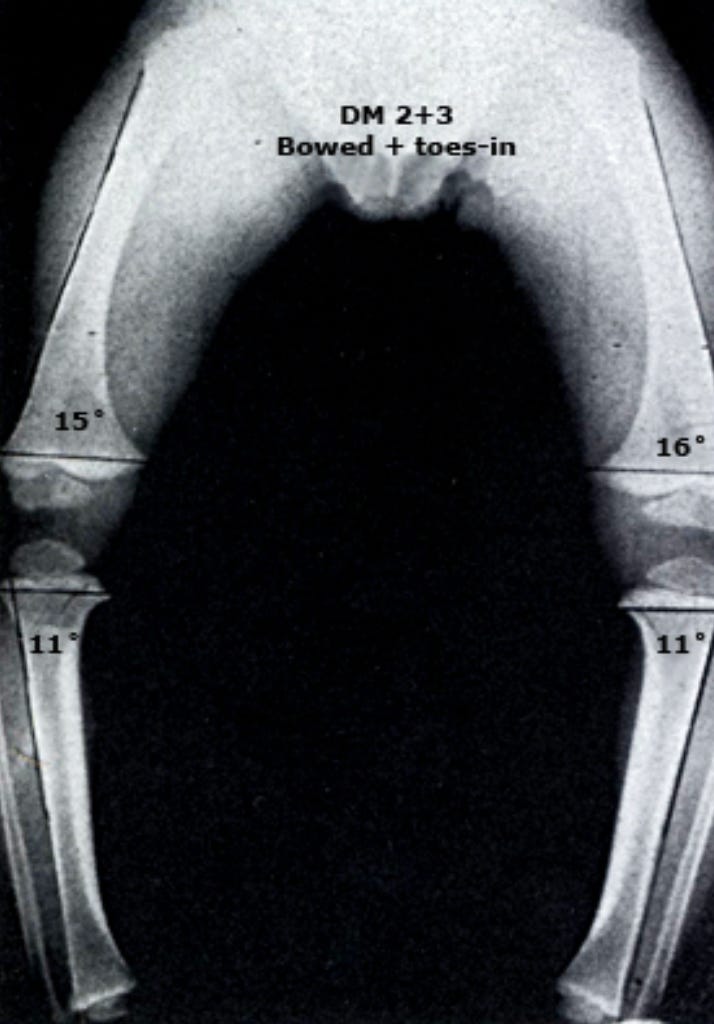

Рентгенологические особенности (при выполнении):

Метафизарно-диафизарный (МД) угол большеберцовой кости: <11°

Соотношение МД углов: бедренный МД угол больше большеберцового МД угла (отношение >1)

МД угол большеберцовой кости >16° (хотя этот признак не является диагностическим)

Соотношение МД углов бедро:голень <1

Метафизарно-диафизарные (МД) углы:

Цель: определение локализации и относительной тяжести деформации

Техника измерения: угол между линией, проведенной через метафиз, и линией, проведенной через диафиз кости

Большеберцовый МД угол >16°: предполагает болезнь Блаунта

Соотношение бедренный МД угол : большеберцовый МД угол:

>1: предполагает физиологическое искривление

<1: предполагает болезнь Блаунта